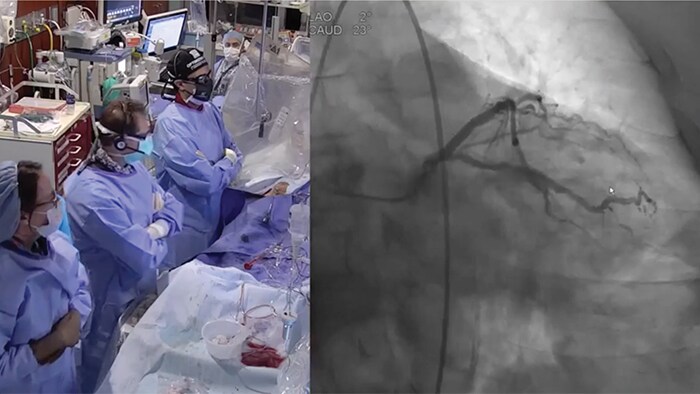

Watch ultra-low contrast PCI contributions from around the world

New data shows that Philips Dynamic Coronary Roadmap has the potential to reduce the use of contrast agent during PCI procedures by 28.8%

New invasive imaging techniques and co-registration software allows PCI to be performed with limited amounts of contrast, even with zero-contrast use, to reduce the risk of CI-AKI for all patients, and especially those with renal insufficiency.